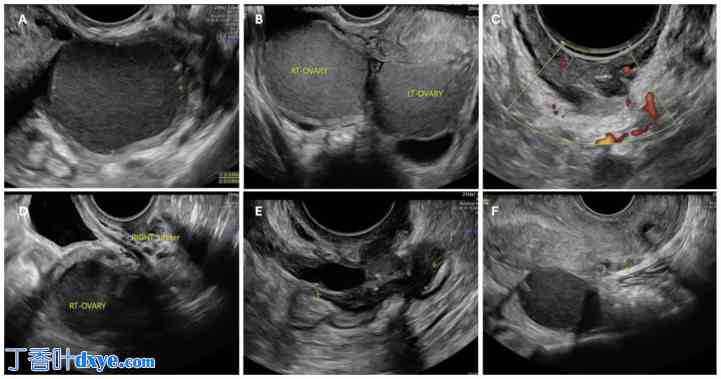

图2.

2.jpg

不同超声诊断的盆腔子宫内膜异位症病例。卵巢受累可为单侧(A)或双侧(B),当两个受累卵巢位于子宫后方时,可呈现特征性的“接吻卵巢”征。宫旁子宫内膜异位症,结节累及右侧输尿管(C)。值得注意的是,盆腔结构位置紧密,因此相邻结构常被子宫内膜异位症侵袭或牵拉,例如输尿管(D、F)。图(E)显示一例直肠前壁子宫内膜异位症。病变通常为多发性,导致表现复杂,可能累及卵巢、宫骶韧带和直肠,从而导致结构活动性减退、Douglas 闭塞,甚至冻骨盆